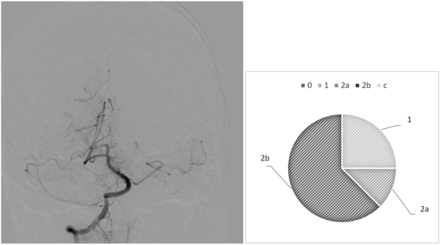

Our analysis highlights diverging behaviors from the raters: In most cases, we observed drastic variability from clusters of raters, which directly questions the existence of a defined mTICI score. For example, case 6 (Fig 1) is an occlusion of the proximal basilar artery with a bilateral fetal configuration of the posterior communicating arteries, which divided the observers. Five of 8 observers (62.5%) assigned the score 2b, 1 (12.5%) gave it a 2a, and 2 (25%) assigned it a score of 1. On the contrary, we observed examples of more consistent analyses, in which the scores were equal or close. This result is demonstrated in case 26 (Fig 2), in which a patent posterior vasculature was achieved following thrombectomy and the analysis was more consensual: mTICI 2b (75%) and 3 (25%).

Case 26, After thrombectomy, interobserver variability.